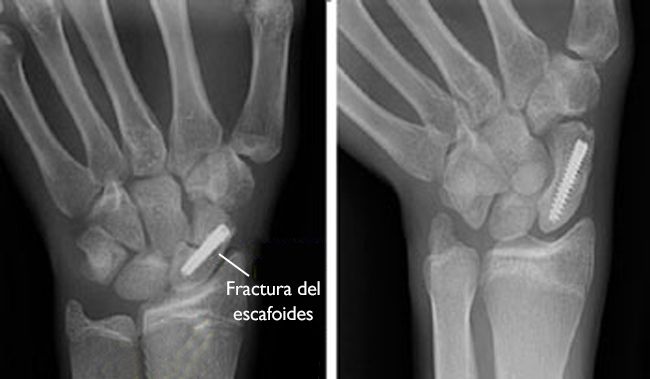

(Izquierda) Esta radiografía muestra una fractura del escafoides fijada en su lugar con la ayuda de un tornillo. (Derecha) Esta radiografía se tomó 4 meses después de la cirugía. La fractura del escafoides ha sanado.

La ubicación y el tamaño de la incisión quirúrgica dependen de qué parte del escafoides está quebrada. A veces, el tornillo o el alambre se pueden colocar en los fragmentos del hueso mediante una pequeña incisión. En otros casos, se requiere de una incisión más grande para garantizar que los fragmentos del escafoides se alineen adecuadamente. La incisión se puede hacer en la parte frontal o posterior de la muñeca.